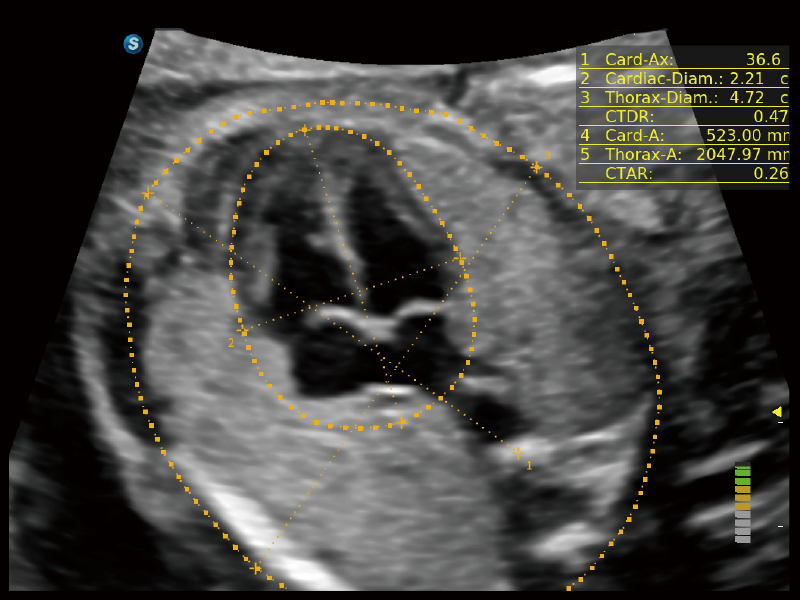

S-Fetus 5.0

S-Fetus (A4C)